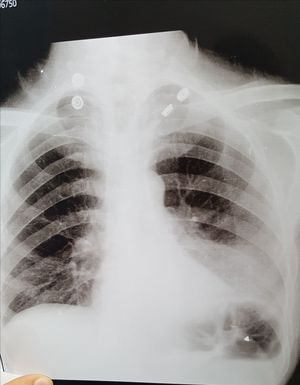

Middle aged pt , with chest pain ,productive cough , and hemoptysis . ECG is normal.

Thanks for all . True answer is left lower lobar collapse. (#The_sail_sign.).. of lt.lower lobe collapse the x-ray chest showed: All the classical features of a tight left lower lobe collapse: 1. Left retrocardiac density shaped like a sail - the 'sail sign' 2. Volume loss in the hemithorax. 3. Inferiorly displaced 'hidden' left hilum. This is due to lung cancer ....